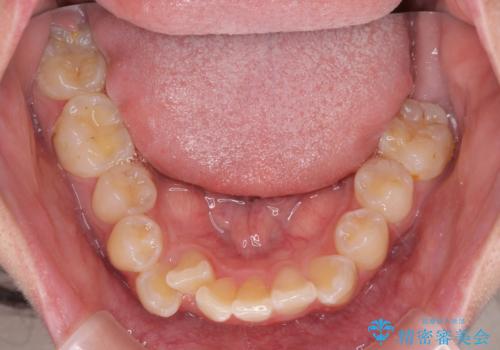

- 審美装置

- 八重歯や埋伏している奥歯など、多くの難しい問題を抱えている患者様です。

重度叢生のため、大臼歯をしっかりと咬合させるために、下顎は左右第二小臼歯を、上顎は前歯部の叢生を解消するために左右第一小臼歯を抜歯し、口元の突出感を改善するために、上顎大臼歯が前方に移動しないようにするために、補助装置による架強固定を行うこととしました。

叢生は思ったよりも早期に改善されましたが、舌の突出癖による上下前歯の非接触が全く改善されず、2年間ほど治療期間が延びる結果となってしまいました。